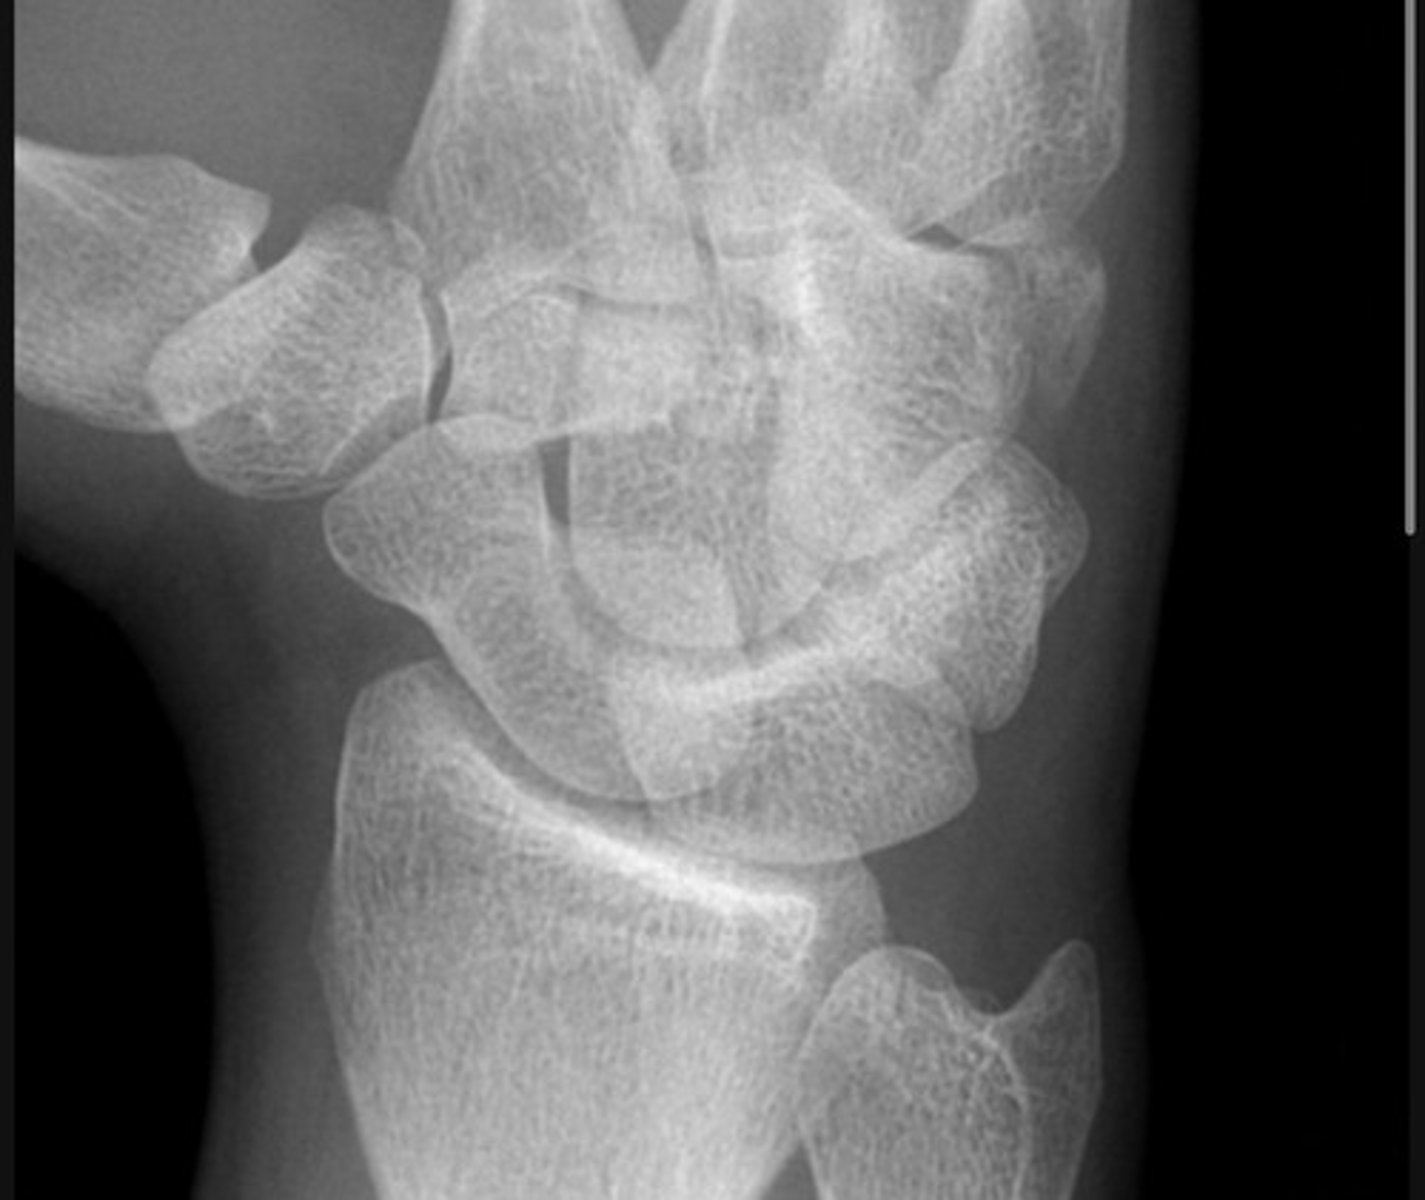

There is a transverse to slightly oblique fracture through the waist of the scaphoid, with no significant displacement or carpal malalignment. Additionally, there is an oblique intra-articular fracture at the base of the first metacarpal, extending into the carpometacarpal joint. The distal metacarpal fragment is displaced proximally and dorsally, consistent with a Bennett's fracture, with associated subluxation at the CMC joint.